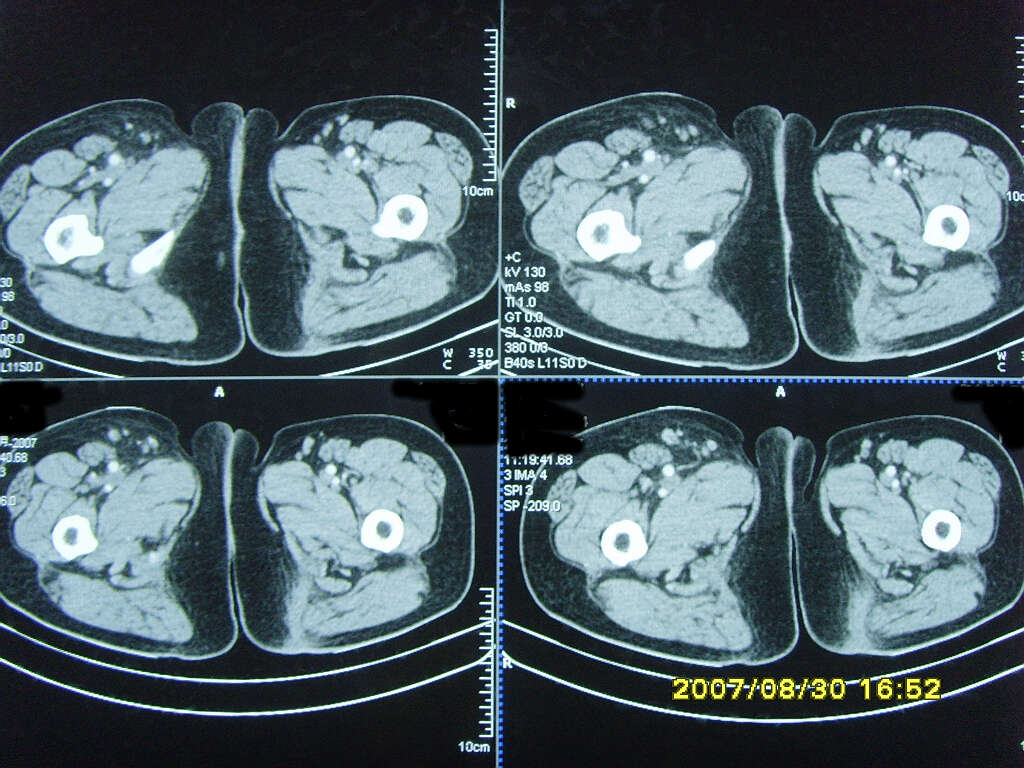

以下是引用zjzjr在2007-9-11 22:21:00的发言:[br]右侧股骨上段前部皮下可见不椭圆形软组织密度影,增强呈环形强化,周围皮下脂肪混浊,考虑感染性病变,不知临床症状如何.